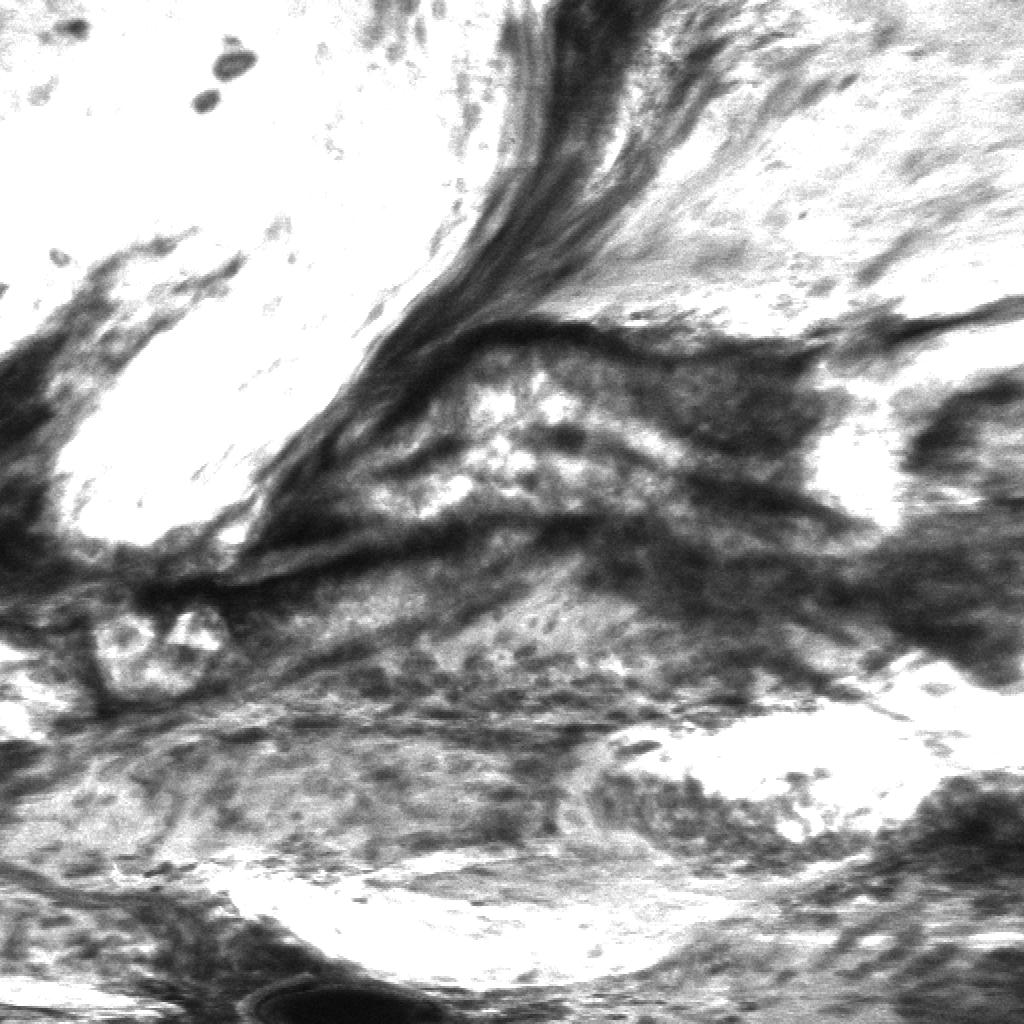

Figure 5: Unsupervised localization of the histopathological features from shallow and deep neurons inside the network. First column (a, e, i) shows the input CLE images from human glioblastoma obtained intraoperatively. Second column (b, f, j) displays activation of neurons from the first layer (conv1, neuron 24) (shallow features); it highlights some of the cellular areas present in the image. Third column (c, g, k) illustrates diagnostic regions of interest identified with sliding window approach. The boxed regions represent high activation of the deepest network neuron. Fourth column (d, h, l) contains images extracted from conv1 activation (neuron 22), representative of the high fluorescence signal, a diagnostic sign of blood-brain barrier disruption and leakage of fluorescent agent from the vessels into the extracellular space.

5.3 Histological features localization

8 out of total 384 reviewed colored neuron activation maps from the first layer were selected for 4 diagnostic CLE images representative for glioma. Selected activation maps highlighted diagnostic tissue architecture patterns in warm colors. Particularly, several maps emphasized regions of optimal image contrast, where hypercellular and abnormal nuclear features could be identified, and would serve as diagnostic features for image classification (Fig. 4.1, columns 2 and 4). Additionally, sliding window method was able to identify diagnostic aggregates of abnormally large malignant glioma cells and atypically hypercellular areas (Fig. 4.1, third column).

Activation of the neurons in the first convolutional layer (conv1) were found to highlight areas with increased fluorescein signal, a sign specific to brain tumor regions. Increased fluorescent signal on CLE images represent areas with blood brain barrier disruption which correspond to the tumor areas visible on a contrast enhanced MR imaging. Interestingly, sliding window method and selected colored activation maps were not distracted or deceived by the red blood cells contamination, as they mostly highlighted tumor and brain cells rather then hypercellular areas due to bleeding. The proposed feature localization approach may be useful in the future to aid in the identification of not only the diagnostic frames, but also directing the surgeon’s attention to the image parts containing major histopathological features.